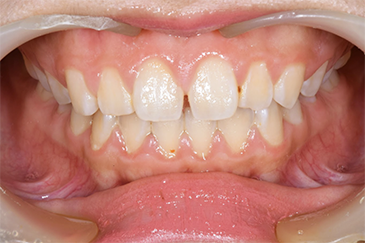

Before

After

| 主訴 | 見た目をきれいにしたい |

| 治療期間 | 6ヶ月 |

| 治療費 | ジルコニアボンド(セラミックの被せもの)165,000円×7(税込み) オフィスホワイトニング4回 3,300円×4(税込み) ホームホワイトニング11,000円 |

| リスク・副作用 | かみ合わせがとても強い方の場合、稀に割れてしまうことがあります。 |

| 先生からの提案 | 上の前歯6本と右下の2番目の歯はセラミックの被せもので治療。 残りの下の前歯5本はプラスチックの材料で虫歯を治療し、 ホワイトニングをおこないました。白くなったご自身の歯の色に合わせてセラミックの 被せものを作成しています。 模型上で完成後をシュミレーションし、上の歯茎の位置をきれいに見えるように 揃えています。(外科処置はしていません) |